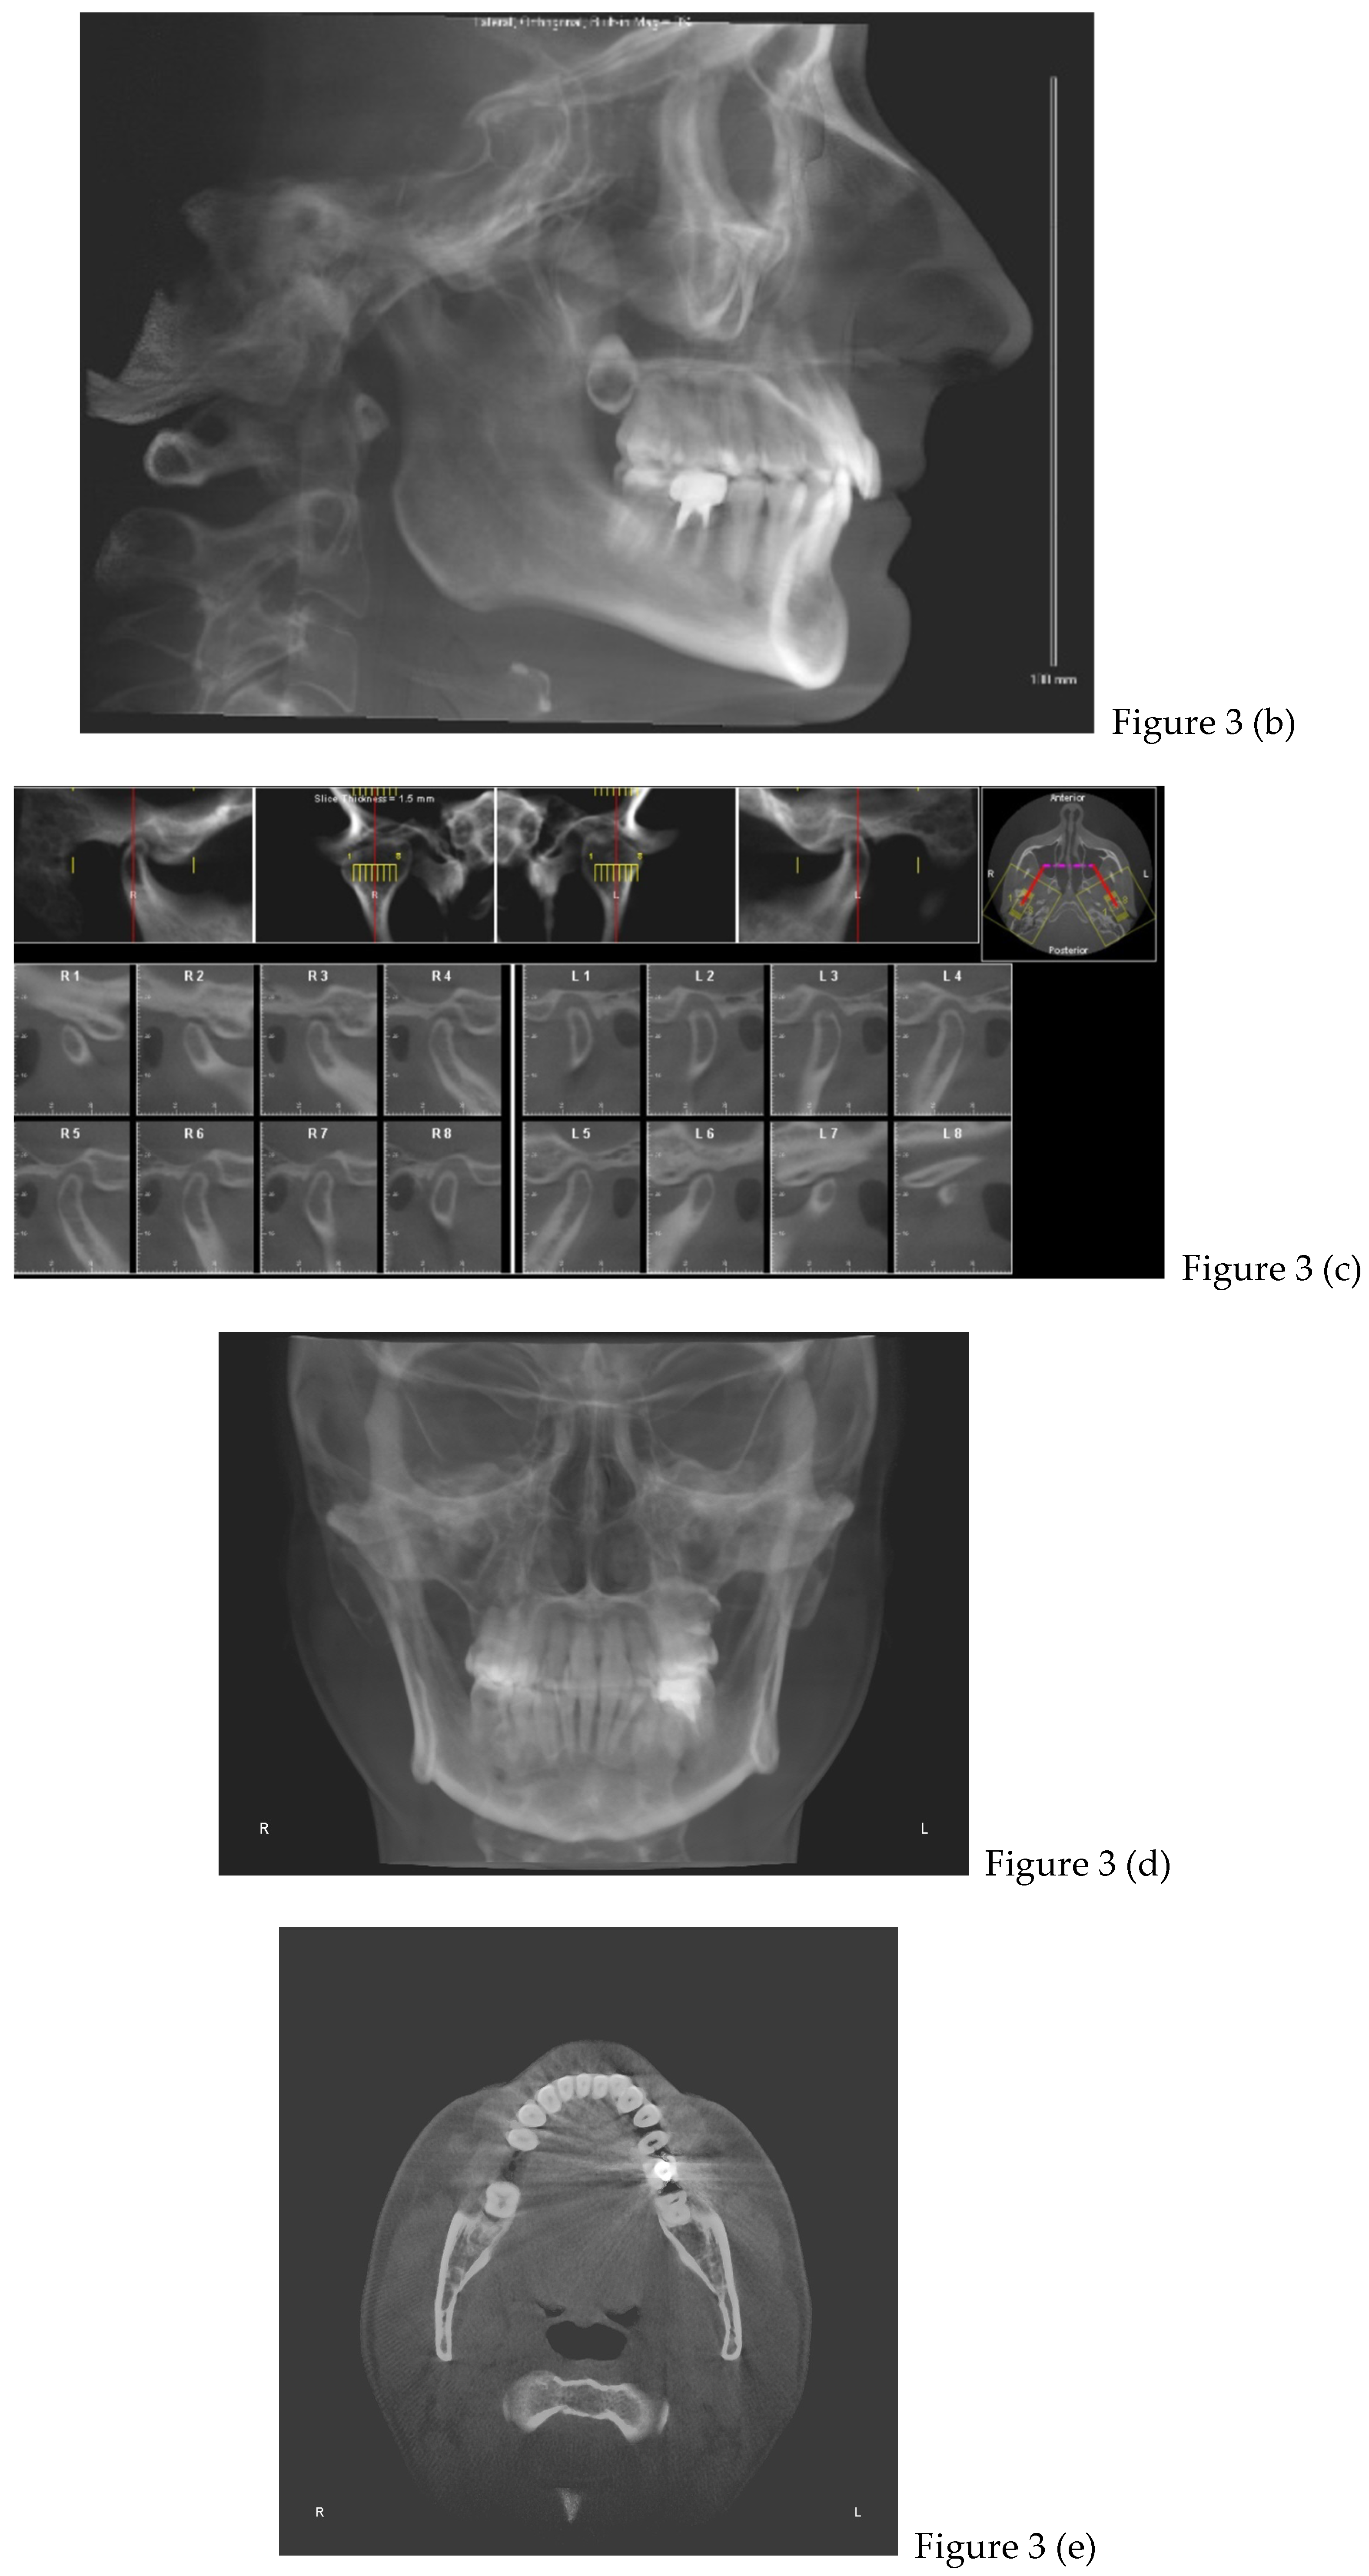

2.2. Cone Beam CT Analysis

| CBCT (t0) | |

| after 8 months | Retainers + CBCT (t1) + final photos |